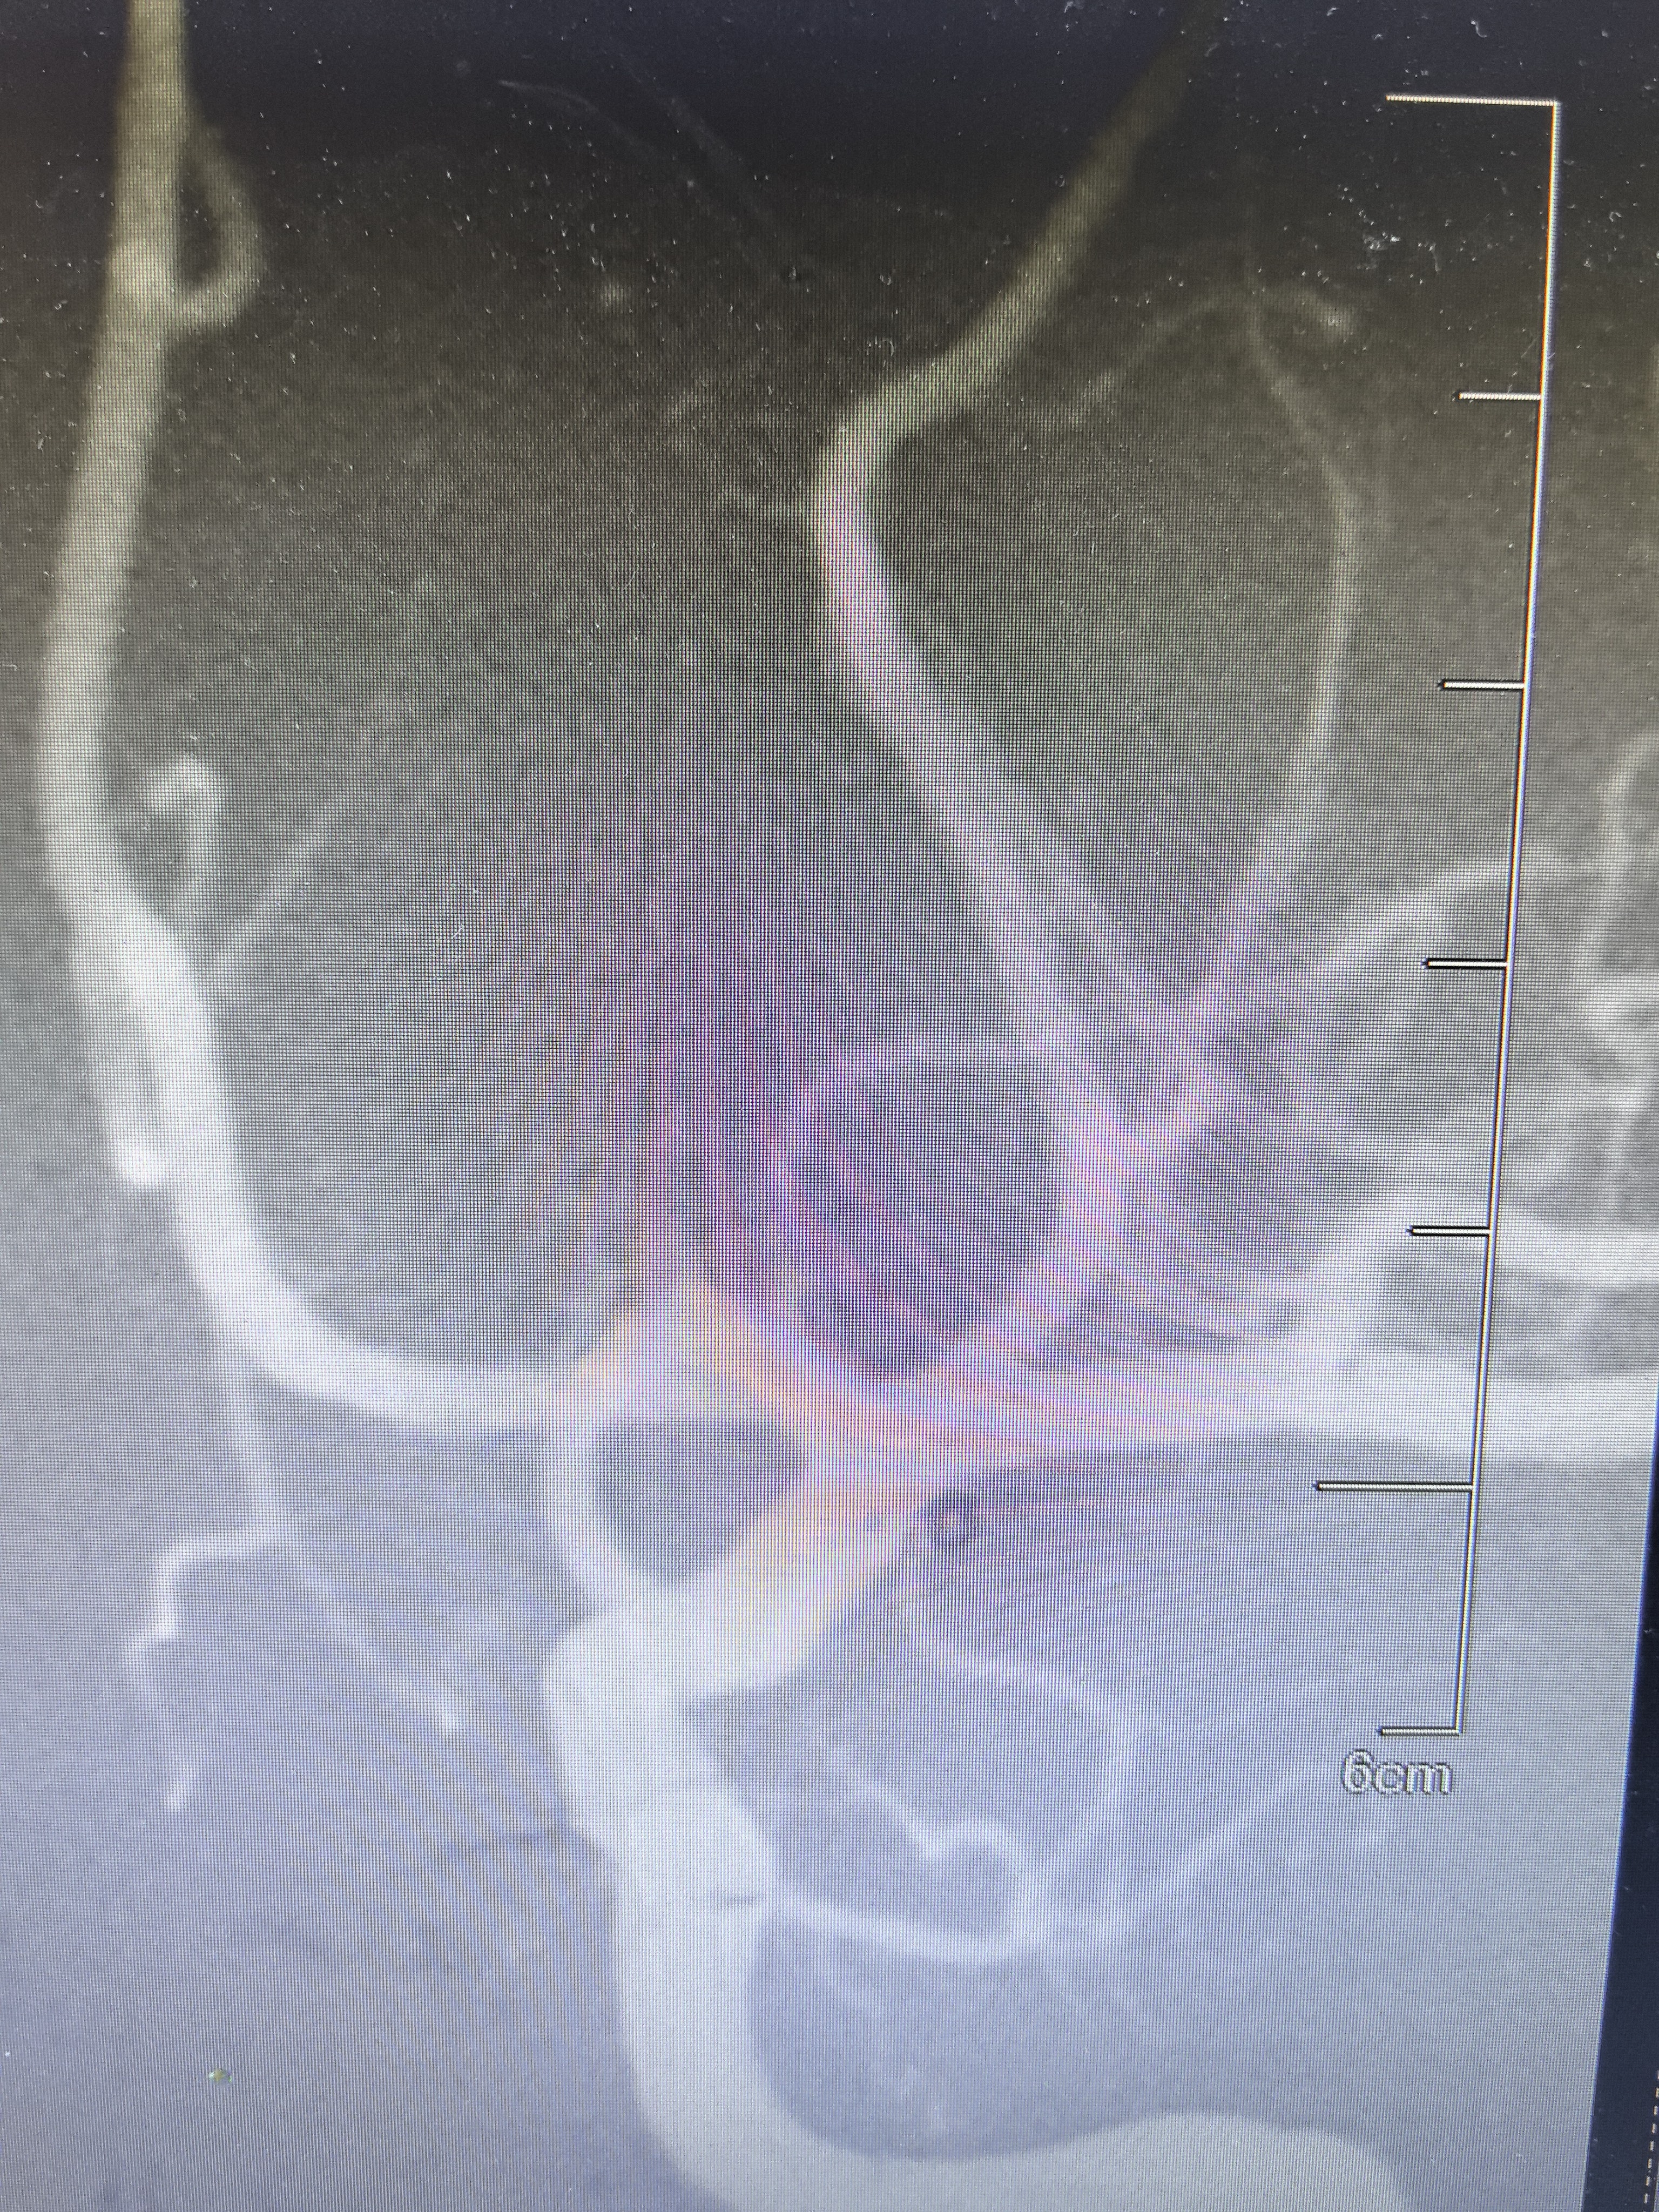

DSA显示左侧变异颞前早期分支起始部微小动脉瘤

路途下显示动脉瘤